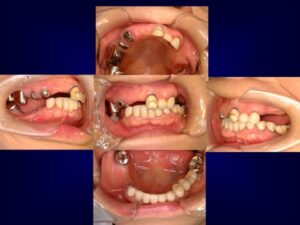

ケース2:上下に多くの問題があった70代後半男性

この方は虫歯や歯周病で残存歯が少なく、グラグラの歯が多い状態でした。最初は保険のクラスプ義歯を入れていたものの安定せず、硬いものを噛めないため外していることが多かったそうです。外見を重視してナイロン義歯を試されましたが、期待したような咬合回復は得られず、全体の再治療を希望して来院されました。

まず全顎の虫歯と歯周病の治療を行い、上顎は残存歯すべてに内冠をかぶせて連結し、全体を支えるテレスコープ義歯を製作しました。装着後は「入れ歯」というよりは取り外し可能な長いブリッジの感覚で、違和感がほとんどないとのことです。

このケースは「残った歯をチーム化して守る」発想が有効であった例です。